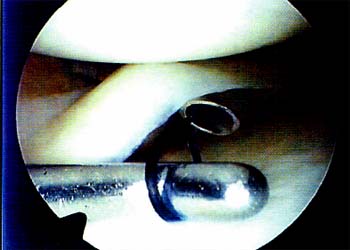

Utilizamos la técnica de afuera-adentro mediante una contraincisión a la altura de la interlínea articular, ingresando el punto con aguja espinal N2 18 perpendicular al trazo lesional. (Foto 2).

Utilizamos la técnica de afuera-adentro mediante una contraincisión a la altura de la interlínea articular,ingresando el punto con aguja espina! Nº 18 perpendicularal trazo lesional(Foto 2).